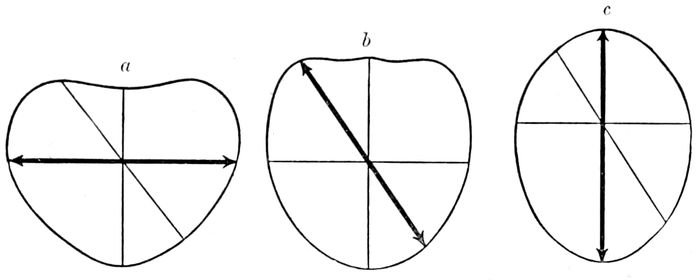

Fig. 2.—The planes of (a) the brim, (b) the cavity and (c) the outlet. (Eden.)

Passing through the brim, a cavity is found below it,

midway between the inlet and outlet, which is nearly

round in shape. This is the “excavation,” or the true

pelvis. Then comes the outlet, bounded in front by the

pubic arch and soft parts, and behind by the coccyx

pushed back as far as it can go. It is ovoid in shape,

but the long axis of this ovoid lies at right angles with

the axis of the ovoid inlet.

20We find, therefore, a succession of three geometric

figures or planes through which the head must pass by

means of a spiral motion called rotation. These figures

are inclined to one another so markedly in front that

a line drawn through the center of each will curve

forward at both ends, one end passing out near the umbilicus,

the other through the vulva. This is known as

the axis of the pelvis or the curve of Carus.